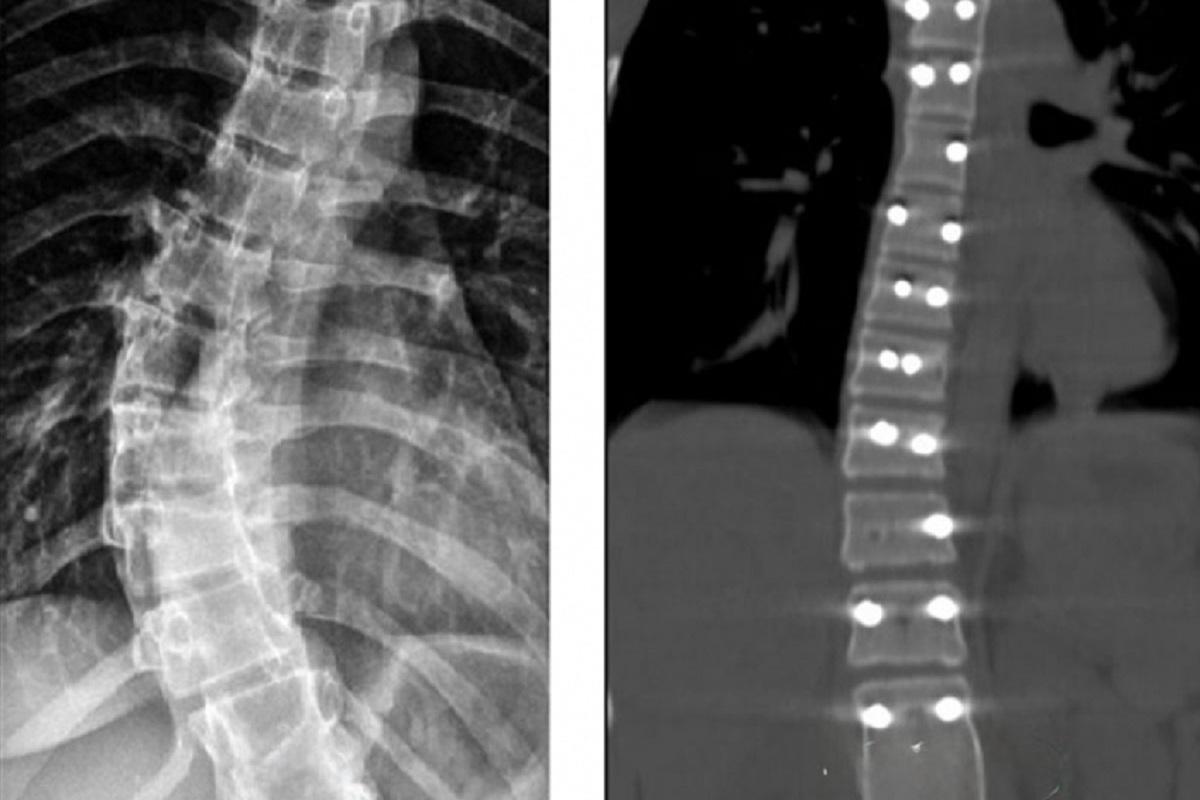

На этот раз медицинская помощь потребовалась 14-летней пациентке, страдающей идиопатическим сколиозом. У нее было диагностировано искривление позвоночника под углом в 40 градусов. Такая деформация со временем могла негативно сказаться на функционировании сердца и легких. Медики приняли решение о проведении операции с целью остановить прогрессирование заболевания и вернуть позвоночнику правильное положение.

В ходе оперативного вмешательства девочке была установлена прочная металлическая конструкция, обеспечивающая фиксацию позвоночника в выпрямленном положении. После операции пациентка быстро восстановилась и была выписана из больницы.